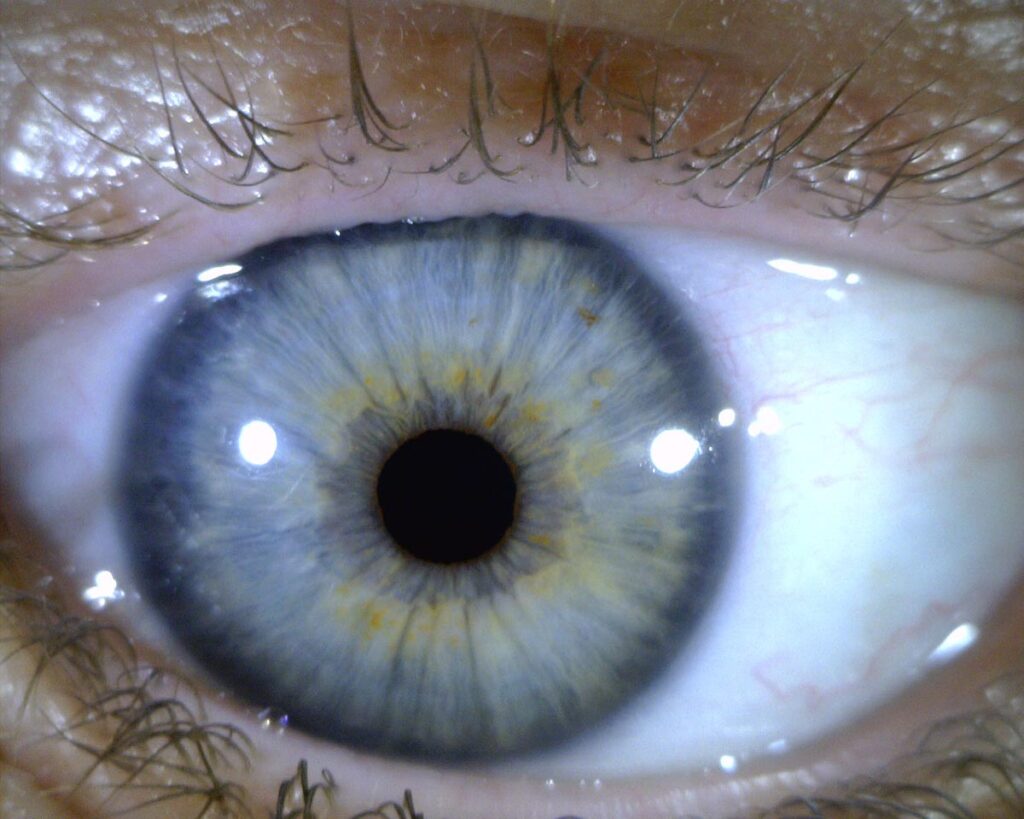

- Registro Ocular

Los dispositivos digitales Dino-Lite están especialmente diseñados para la captura, documentación y visualización de alta resolución del iris en pantalla. Su diseño ergonómico incorpora un cabezal de apoyo orbital que asegura de forma pasiva la distancia focal exacta, garantizando un enfoque milimétrico y cómodo para el usuario sin contacto directo con el globo ocular.

Equipados con tecnología de iluminación LED conmutable mediante software, estos sistemas integran luces amarillas y blancas. Los LEDs amarillos mitigan el rebote lumínico en ojos de tonalidad oscura, brindando un registro visual superior del micro-relieve y la textura del iris.